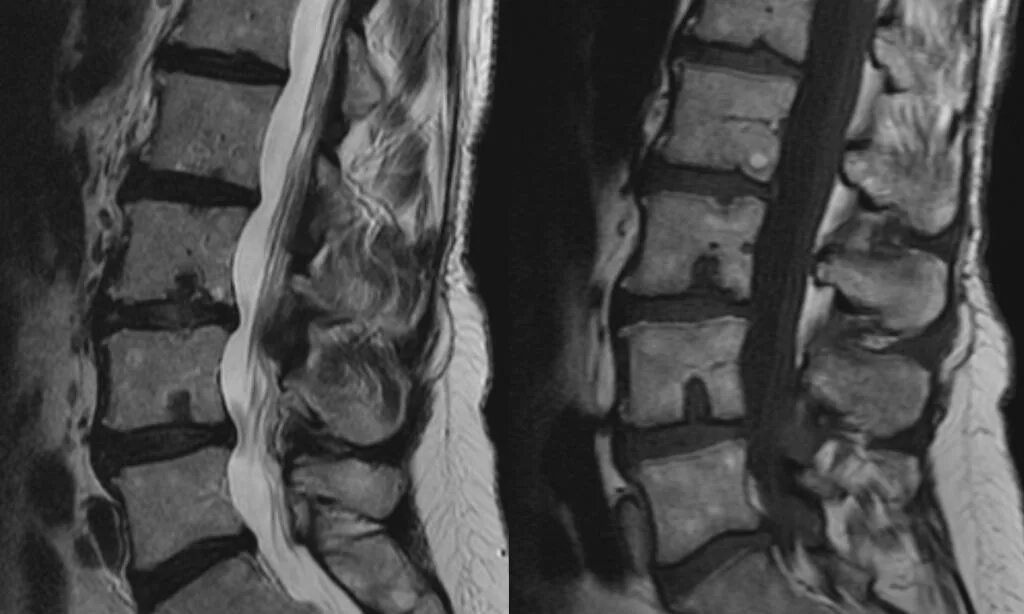

Узлы шморля в грудном отделе что это